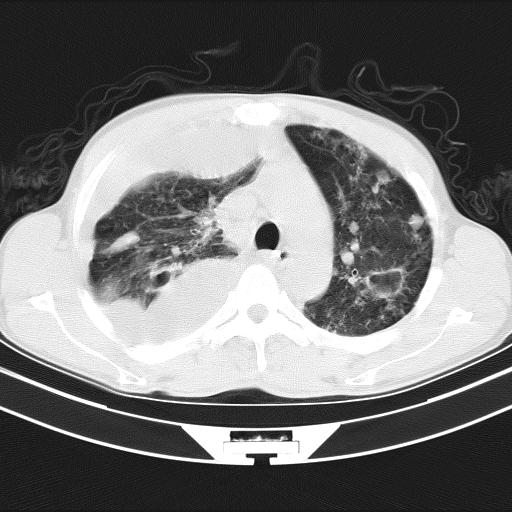

男性,44岁,结核病史多年。现胸闷气短,咳嗽,偶咳血。

右侧胸腔积液

右肺下叶不张

双肺多发结节影最分空洞形成考虑占位不除外结核

双肺陈旧性病变

1、右侧大量胸腔积液伴右肺压缩性膨胀不全,建议抽液治疗后复查 2、两肺继发性tb伴空洞形成。

1)两肺继发性肺结核伴空洞形成,左肺多发性结核球。2)右侧大量胸腔积液伴右肺部分膨胀不全。3)纵隔淋巴结肿大。